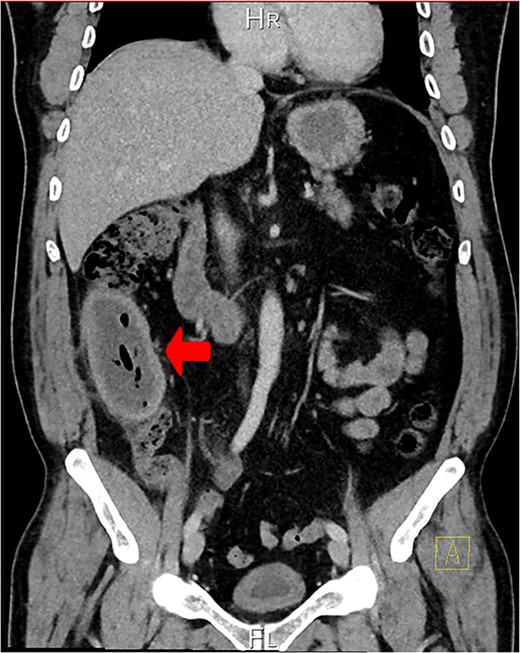

A CT scan showed an oval, 13 × 5.2 cm mass in the right iliac fossa arising from the cecum and running upward, with a thick, edematous wall, fluid, gaseous content, and extensive fat stranding. There was no free fluid and no dilation of bowel, suggesting appendicitis (Figs 1 and 2). Due to these findings, the patient underwent an emergency laparoscopic appendectomy that was converted to open laparotomy. The patient ended up with a right hemicolectomy instead of appendectomy as the appendix could not be separated from the mass, with no separation line between the mass and the cecum. The mass (Fig. 3) measured 10 × 7 × 7 cm and had a thick wall and pyogenic membrane.

Cross-sectional CT view shows the mass measuring 13 × 5.2 cm with significant wall thickening measuring 14.2 mm and fat stranding. The contents are a mixture of fluid and gas, consistent with appendicitis.